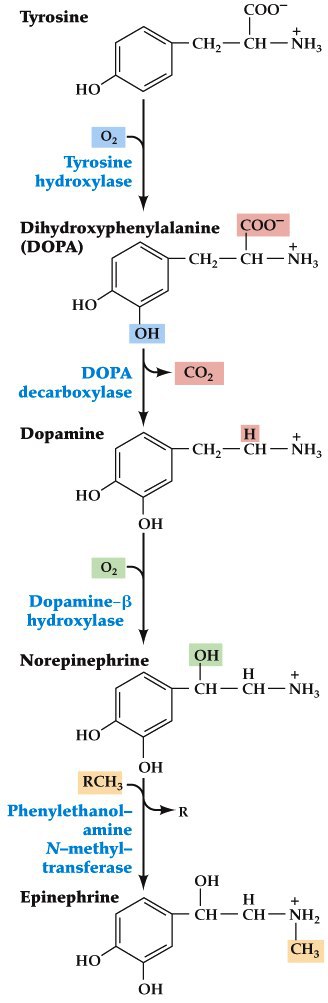

Dopaminergic neurons modulate direct and indirect pathways

- Medium spiny neurons (MSNs) in striatum project to the substantia nigra pars compacta (SNc), which in turn projects back to MSNs

- Both MSNs that project to GPe and GPi receive these inputs

- Those that project to GPi have type D1 receptors (coupled to a Gαs, excitatory) and those that project to GPe use type D2 receptors (Gαi, inhibitory)

- Dopamine excites the direct and inhibits the indirect pathway

Parkinson’s disease

- Due to the degeneration of dopaminergic neurons of the substantia nigra pars compacta

- Leads to tremors, slowness of movements, rigidity of extremities and neck, minimal facial expressions

- Slowly progressing disease

- Some success in slowing the progression comes from the use of Levadopa (L-DOPA)– gets converted to dopamine and gets to dopamine receptors in basal ganglia

Treatments for Parkinson’s

- Dopamine can’t cross the blood brain barrier but L-DOPA can

- Deep brain stimulation

- Cell replacement therapy– implant dopamine making neurons into the striatum